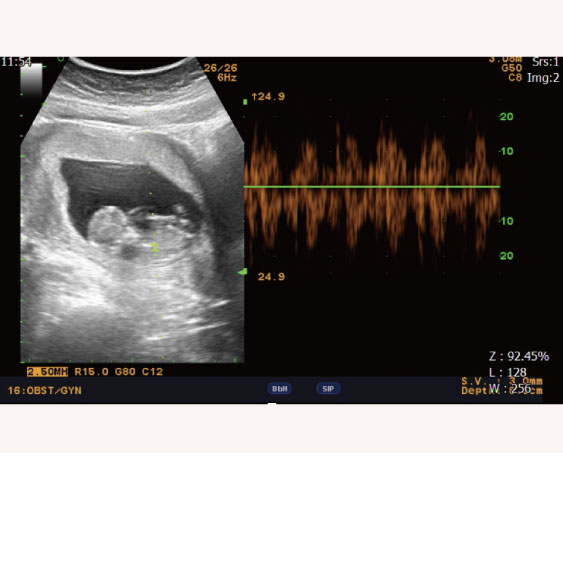

MIRA找出妳的植入時程 2023-12-28

婚後懷孕未果 著床時間異於常人

夫妻婚後未孕且AMH值低,利用MIRA檢測子宮內膜狀態,發現著床時間異於常人,調整後成功生下女寶寶。祝福新手爸媽